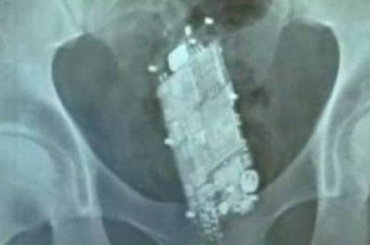

Um reeducando do Centro de Ressocialização de Sorriso escondeu no anus um aparelho de celular com receio de perde-lo durante revista nas celas. Entretanto, o aparelho foi descoberto. A situação ocorreu no final da tarde de quarta-feira (30).

Segundo o site MTNotícias, o reeducando se queixava de fortes dores. Os agentes ainda tentaram retirar o aparelho no Centro de Ressocialização solicitando que o reeducando se agachasse, porém não houve êxito.

O rapaz foi encaminhado ao Hospital Regional de Sorriso.